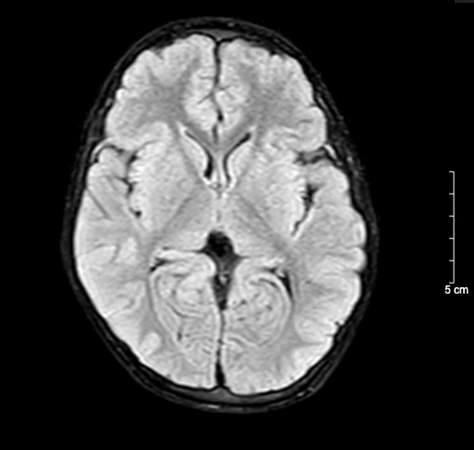

Kết quả chụp não, cột sống cổ bệnh nhi sau 5 ngày nhập viện bình thường

BSCKII. Doãn Phúc Hải - Trung tâm Nhi khoa, Bệnh viện Bạch Mai trực tiếp điều trị cho bệnh nhi chia sẻ: Thân nhiệt của bệnh nhi được hạ nhanh xuống và kiểm soát duy trì ở mức 34°C, giảm tổn thương, tái tưới máu tại não, tăng tỉ lệ sống và hồi phục chức năng thần kinh. Sau 72 giờ điều trị hạ thân nhiệt chủ động, bệnh nhi được nâng thân nhiệt, làm ấm trở lại về mức bình thường và duy trì theo dõi trong 48 giờ. Khi thân nhiệt trở lại bình thường, bệnh nhi tỉnh dần và được rút ống thở. Dấu hiệu sinh tồn ổn định, tri giác nhận thức tốt. Sau 5 ngày nằm viện, bệnh nhi đã tỉnh táo hoàn toàn. Kết quả chụp tim, phổi, MRI sọ não, cột sống cổ không thấy bất thường. Đây cũng là trường hợp đầu tiên trẻ 5 tuổi tự “thắt cổ” mà chúng tôi bắt gặp.

Kết quả chụp não, cột sống cổ bệnh nhi sau 5 ngày nhập viện bình thường

BSCKII. Doãn Phúc Hải - Trung tâm Nhi khoa, Bệnh viện Bạch Mai trực tiếp điều trị cho bệnh nhi chia sẻ: Thân nhiệt của bệnh nhi được hạ nhanh xuống và kiểm soát duy trì ở mức 34°C, giảm tổn thương, tái tưới máu tại não, tăng tỉ lệ sống và hồi phục chức năng thần kinh. Sau 72 giờ điều trị hạ thân nhiệt chủ động, bệnh nhi được nâng thân nhiệt, làm ấm trở lại về mức bình thường và duy trì theo dõi trong 48 giờ. Khi thân nhiệt trở lại bình thường, bệnh nhi tỉnh dần và được rút ống thở. Dấu hiệu sinh tồn ổn định, tri giác nhận thức tốt. Sau 5 ngày nằm viện, bệnh nhi đã tỉnh táo hoàn toàn. Kết quả chụp tim, phổi, MRI sọ não, cột sống cổ không thấy bất thường. Đây cũng là trường hợp đầu tiên trẻ 5 tuổi tự “thắt cổ” mà chúng tôi bắt gặp.